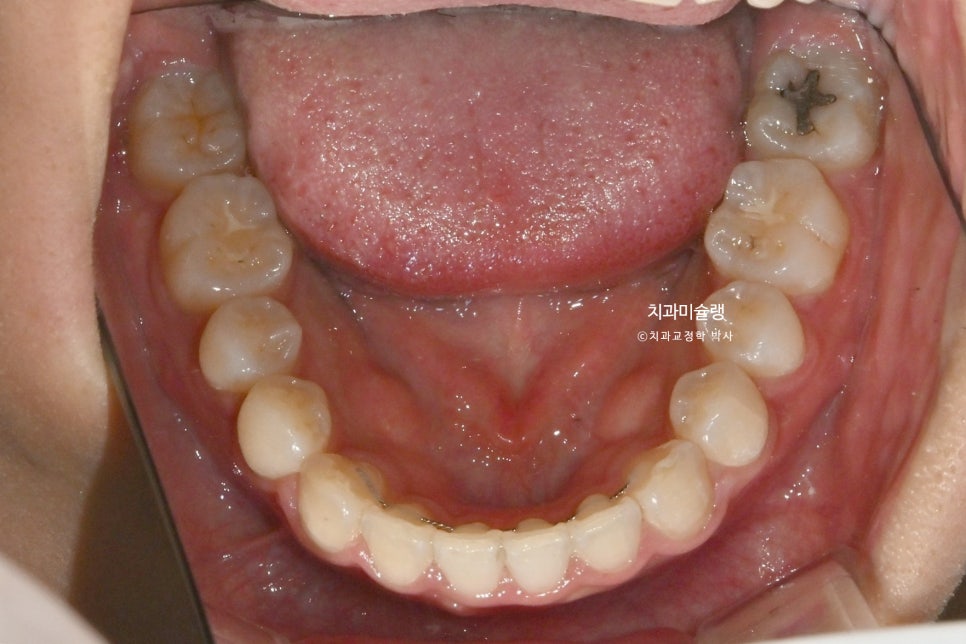

치료 완료: 1년 3개월째

치료시작 1년 3개월째, 원하는 바가 모두 달성되어 장치를 뗍니다.

중심선은 잘 맞으며

어금니 교합은 1급 교합관계를 보입니다.